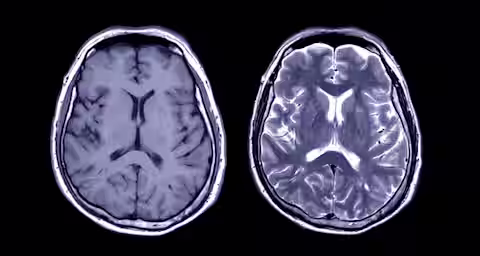

A brain injury will affect an individual in many different ways. It is imperative that rehabilitation and treatment is tailored to that particular individual. A treatment programme will need to change to recognise progress made or indeed, lack of progress. A person with a brain injury may therefore use a number of different facilities at different stages of recovery.